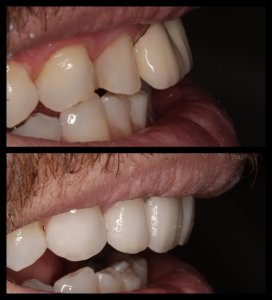

ΠΡΟΣΘΕΤΙΚΕΣ ΑΠΟΚΑΤΑΣΤΑΣΕΙΣ ΜΕ ΣΥΝΔΥΑΣΜΟ ΛΕΥΚΑΝΣΗΣ, ΣΥΝΘΕΤΩΝ ΡΗΤΙΝΩΝ ΚΑΙ ΟΛΟΚΕΡΑΜΙΚΩΝ ΟΨΕΩΝ ΚΑΙ ΣΤΕΦΑΝΩΝ